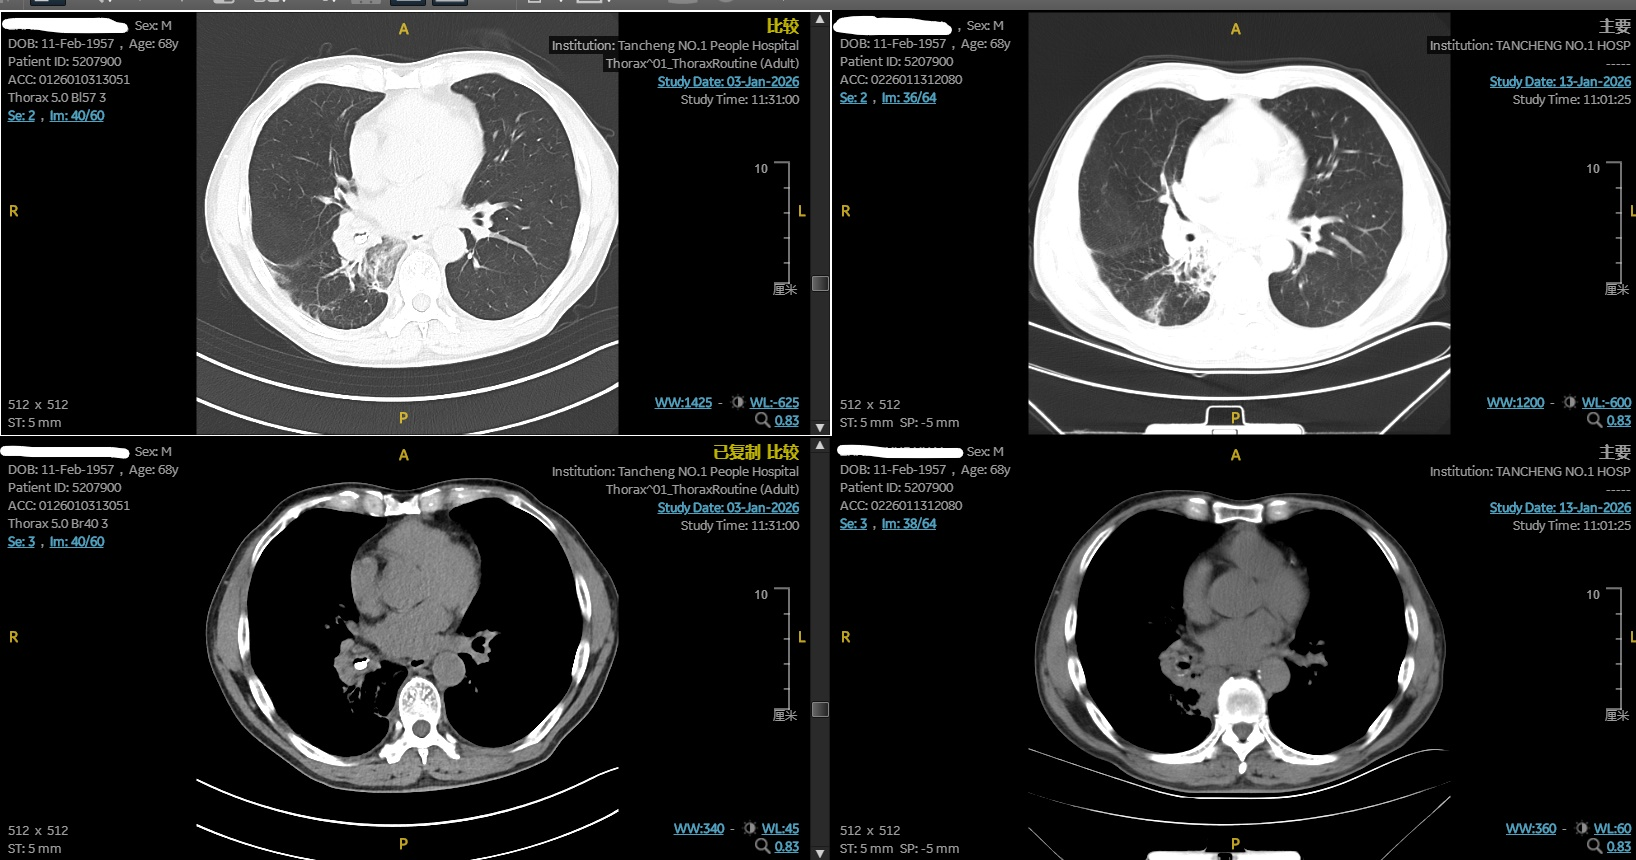

术前CT显示右下叶支气管异物,术后CT显示异物已取出。